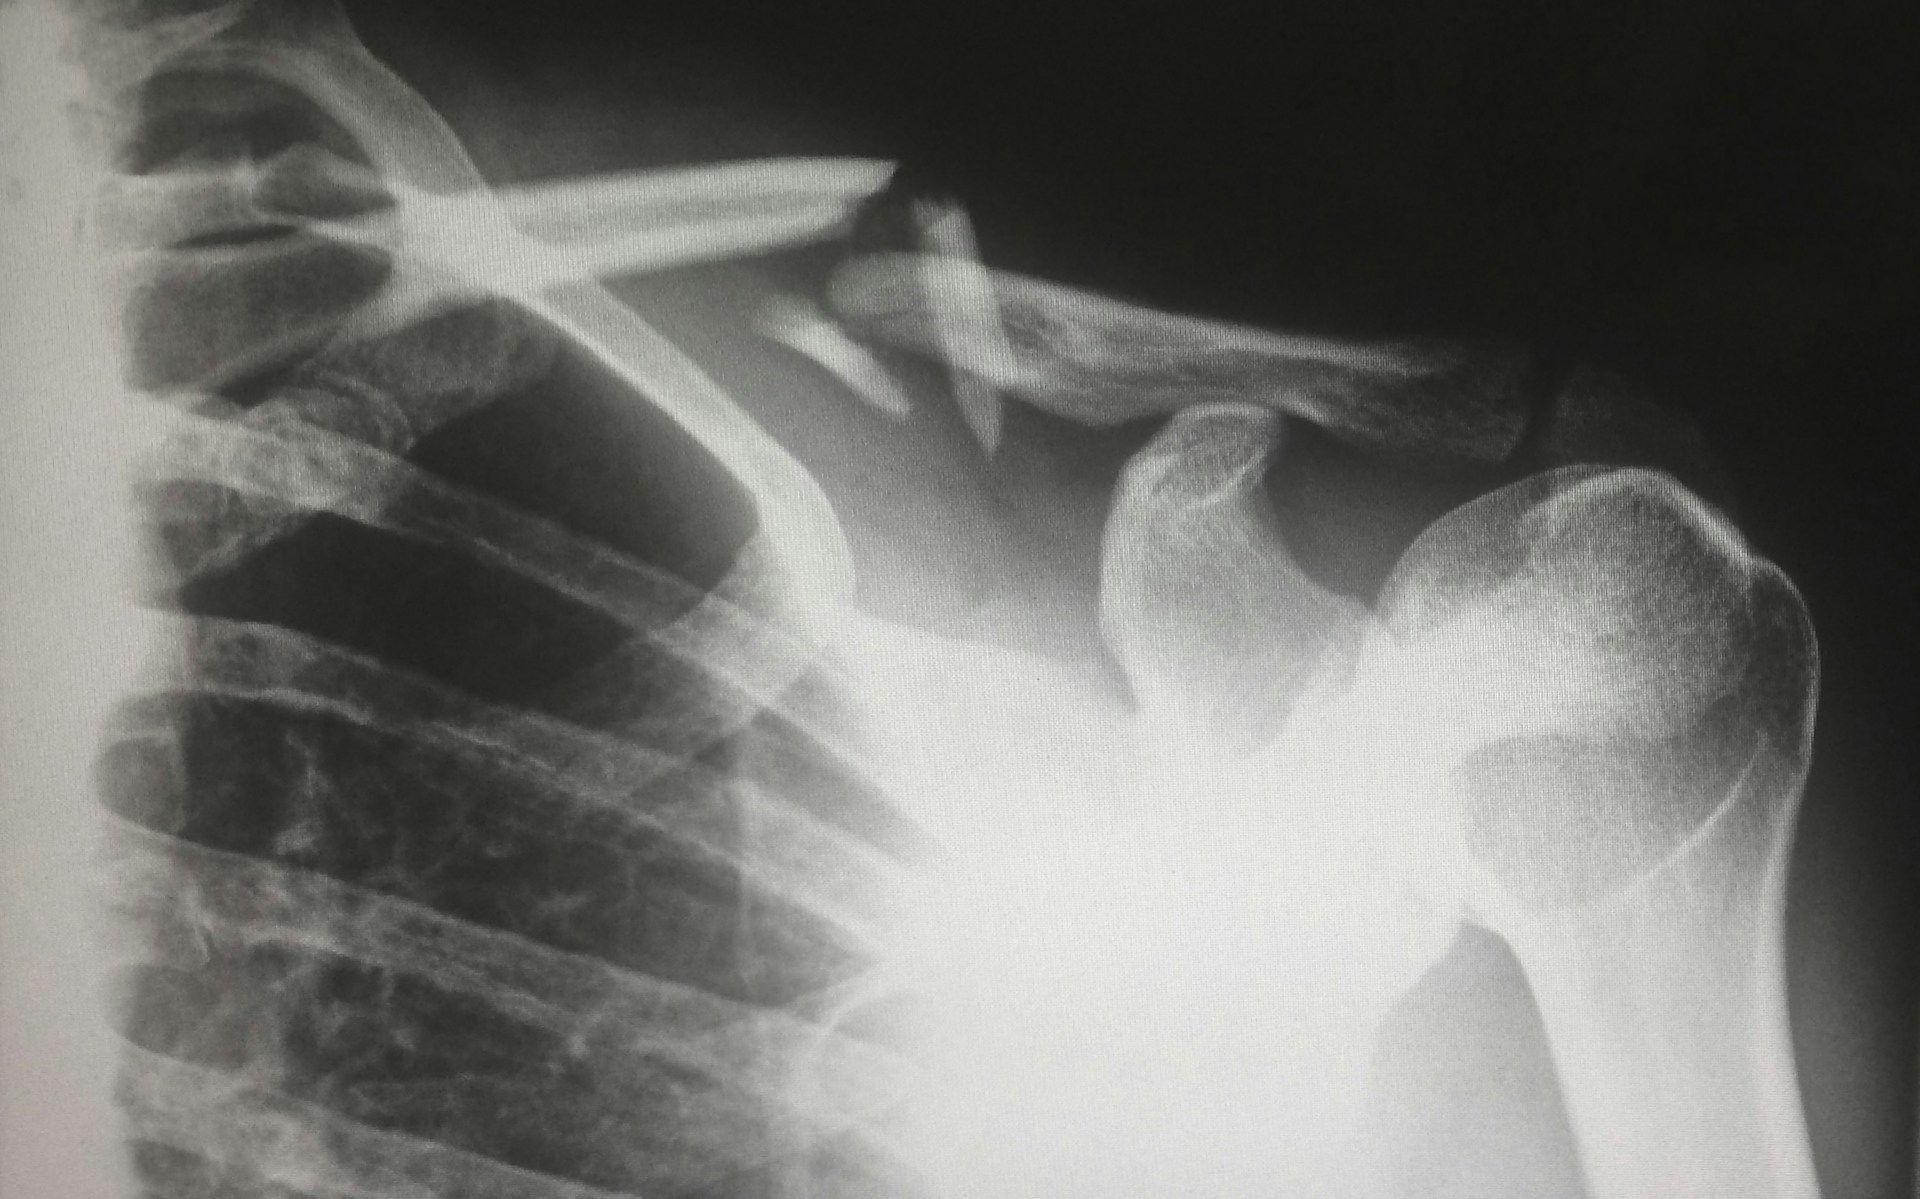

Определить тип перелома не сложно. Если кожа разорвана, а поврежденную кость видно перелом называется открытым. Если же кожа остается неповрежденной, перелом считается закрытым.

Классифицировать переломы можно по разным критериям: по направлению линии разлома (продольные, поперечные), по месту повреждения (в области тела кости, головки) и по степени тяжести (со смещением или без него).